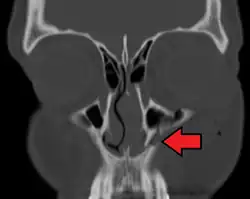

A maxilla fracture is a form of facial fracture. A maxilla fracture is often the result of facial trauma such as violence, falls or automobile accidents. Maxilla fractures are classified according to the Le Fort classification.